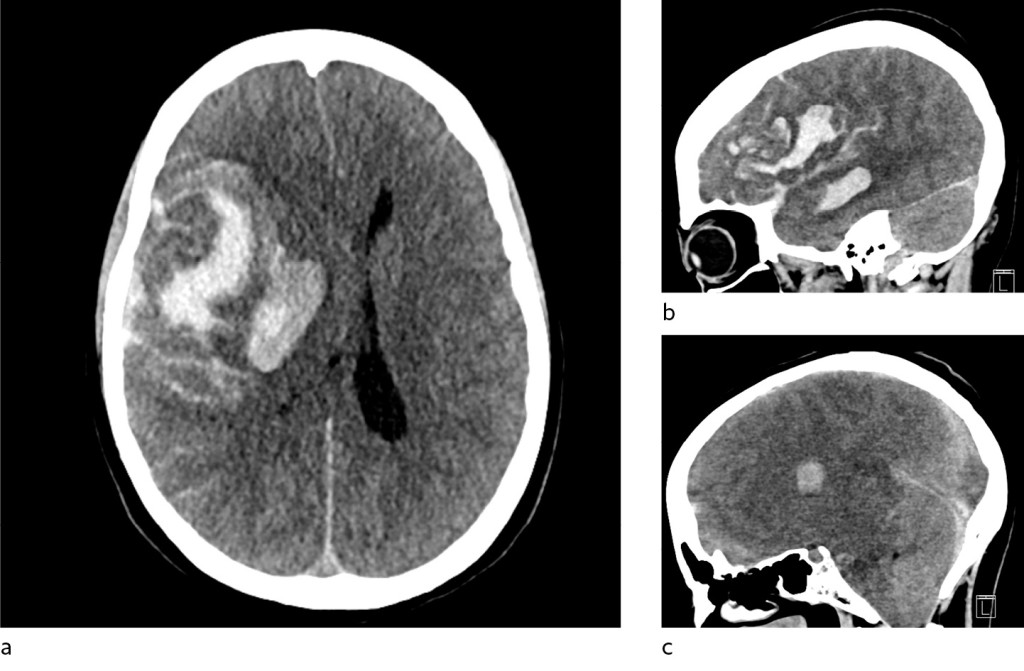

The patient arrived at the university hospital three hours after notification by the local hospital. Upon admission, the patient had bilateral mydriasis with no reaction to light. Treatment with mannitol was initiated, and a CT of the head taken immediately after arrival showed progression of a major intracranial haemorrhage with incipient herniation (Figure 2). Cerebral angiography (TCD) was consistent with cessation of blood circulation in the brain, and further interventions were considered futile.

Figure 2 CT of the patient's head at the university hospital showed increased haematoma, a) axially, b) sagittally and c)…

Figure 2 CT of the patient's head at the university hospital showed increased haematoma, a) axially, b) sagittally and c) sagittally near the midline. There is now both transtentorial herniation and herniation of cerebellar tonsils through the foramen magnum. Low density in the cerebral cortex and reduced differentiation between grey and white matter are signs of global hypoxia.

A few days after this incident, Oslo University Hospital, Rikshospitalet reported multiple cases of severe blood clots and bleeding in patients who had received an identical vaccine. These patients also had low platelet counts, and in these cases a link was found between the events and the vaccine (1). Since then, the condition has been referred to as vaccine-induced immune thrombotic thrombocytopenia (VITT), which is characterised by low platelet counts, thrombus formation and antibodies to PF4 (1, 5). In light of this knowledge, new investigations were carried out, and our patient was also found to have a tendency towards thrombus formation with small thrombi in the transverse sinus, frontal lobe and pulmonary artery. Antibodies to PF4 were also detected. Overall, there is therefore a strong indication that this was a case of VITT. Retrospectively, it has to be asked whether the bleeding seen on the CT images represented a venous haemorrhagic infarction similar to that seen in several patients at Rikshospitalet (1), and whether the bleeding component may have been predominant as a result of VITT. A venous infarction might explain the patient's headache.